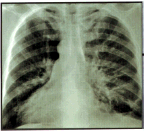

- A case-control study of lung cancer patients and healthy control subjects

suggests that genetic variants of a receptor for a common brain chemical

known as dopamine influence the probability of smoking addiction in both

groups of subjects, according to Dr. Margaret R. Spitz, chairman of the

Department of Epidemiology at M. D. Anderson and lead author of the National

Institutes of Health-funded study.